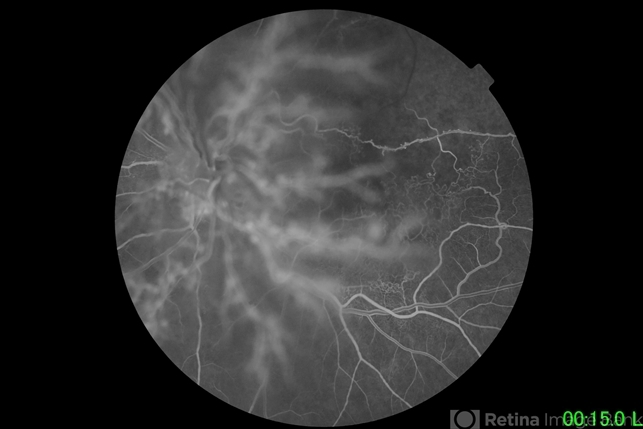

- branch retinal vein occlusion (BRVO)

- Narciso Atienza, Jr. MD, MBA

Fundus camera

Topcon - Description

- 72-year-old female with ischemic branch retinal vein occlusion. Neovascular proliferation on the posterior hyaloid. Background shows ischemic BRVO with florid neovascularization emanating from the disc.